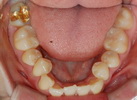

| ÃæÄ¡Ä¡·á Àη¹ÀÌ¿Í Å©... |